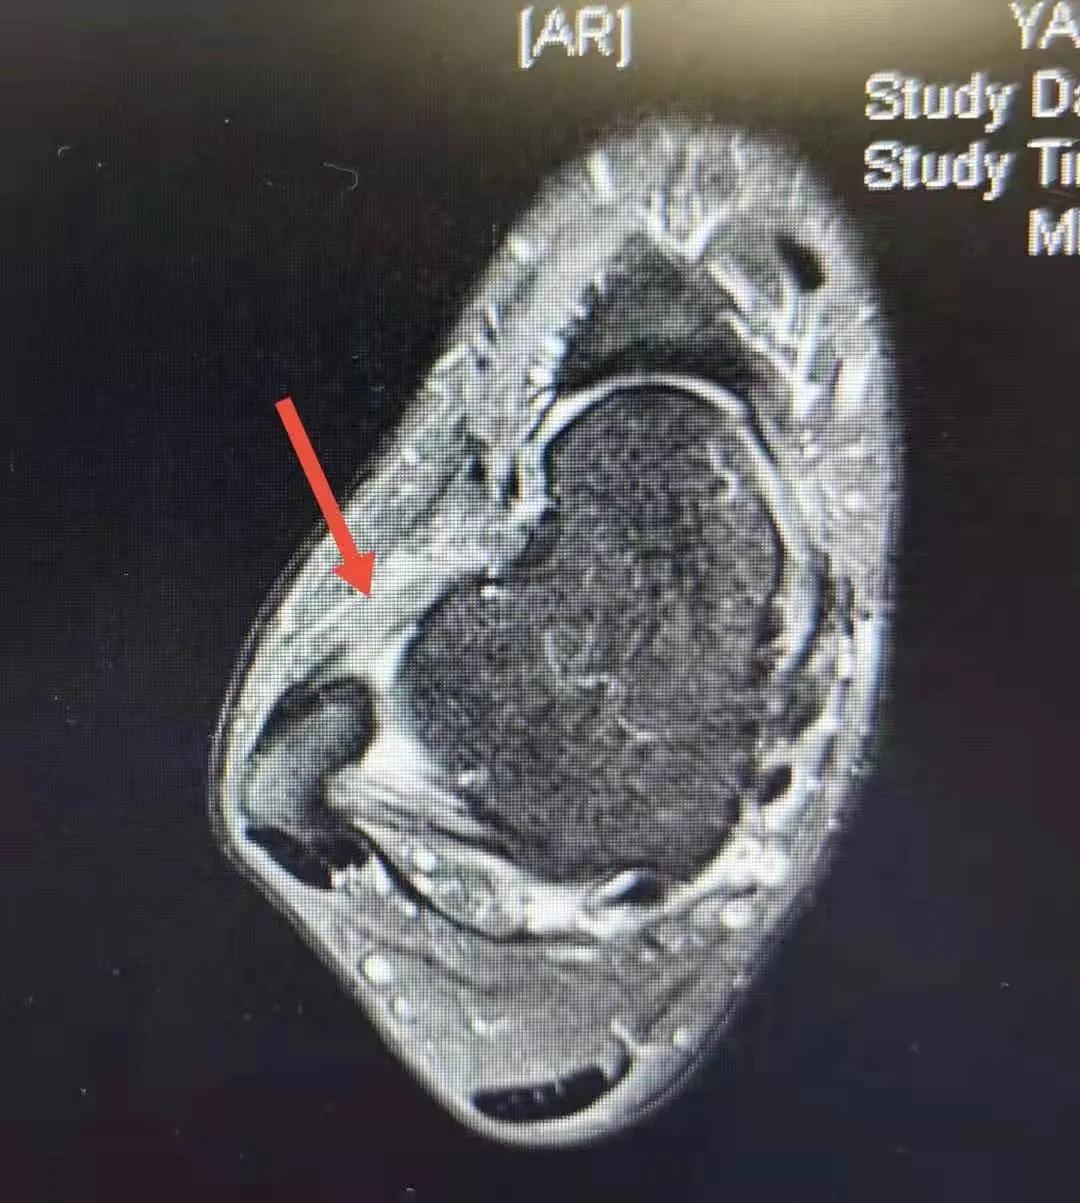

我自己曾经左侧脚外踝的韧带完全断裂过,就是经过了10个月才完全恢复比较正常的体育运动,我有亲身的体会。结合这些体会和对患者的检查,初步判断患者韧带没有恢复好,正在康复期间。为了验证这个判断,我们让患者进行了核磁共振检查。核磁检查后的片子为下图(黑白*图色**),箭头指示的是距腓前韧带损伤后的增粗,信号增高,是正在愈合过程中的表现。